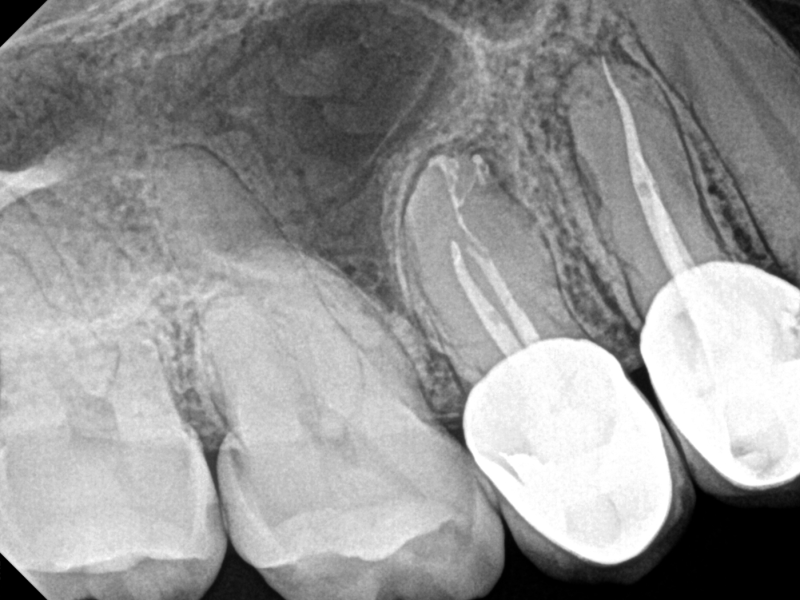

Complex Anatomy

Complex Anatomy with Healing Evidence

Nestor Cohenca, DDS, FIADT

View Case Images